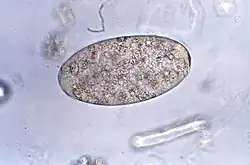

L'identification microscopique des œufs, ou plus rarement des adultes, dans les selles ou les vomissements constitue la base du diagnostic spécifique. Les œufs sont indiscernables de ceux de la douve du foie très étroitement apparentée, mais cela est en grande partie sans conséquence puisque le traitement est, pour l'essentiel, identique dans les deux cas.